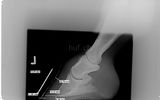

Bildergalerie Orthopädie

Vergrössertes Bild und Kommentar per Klick...